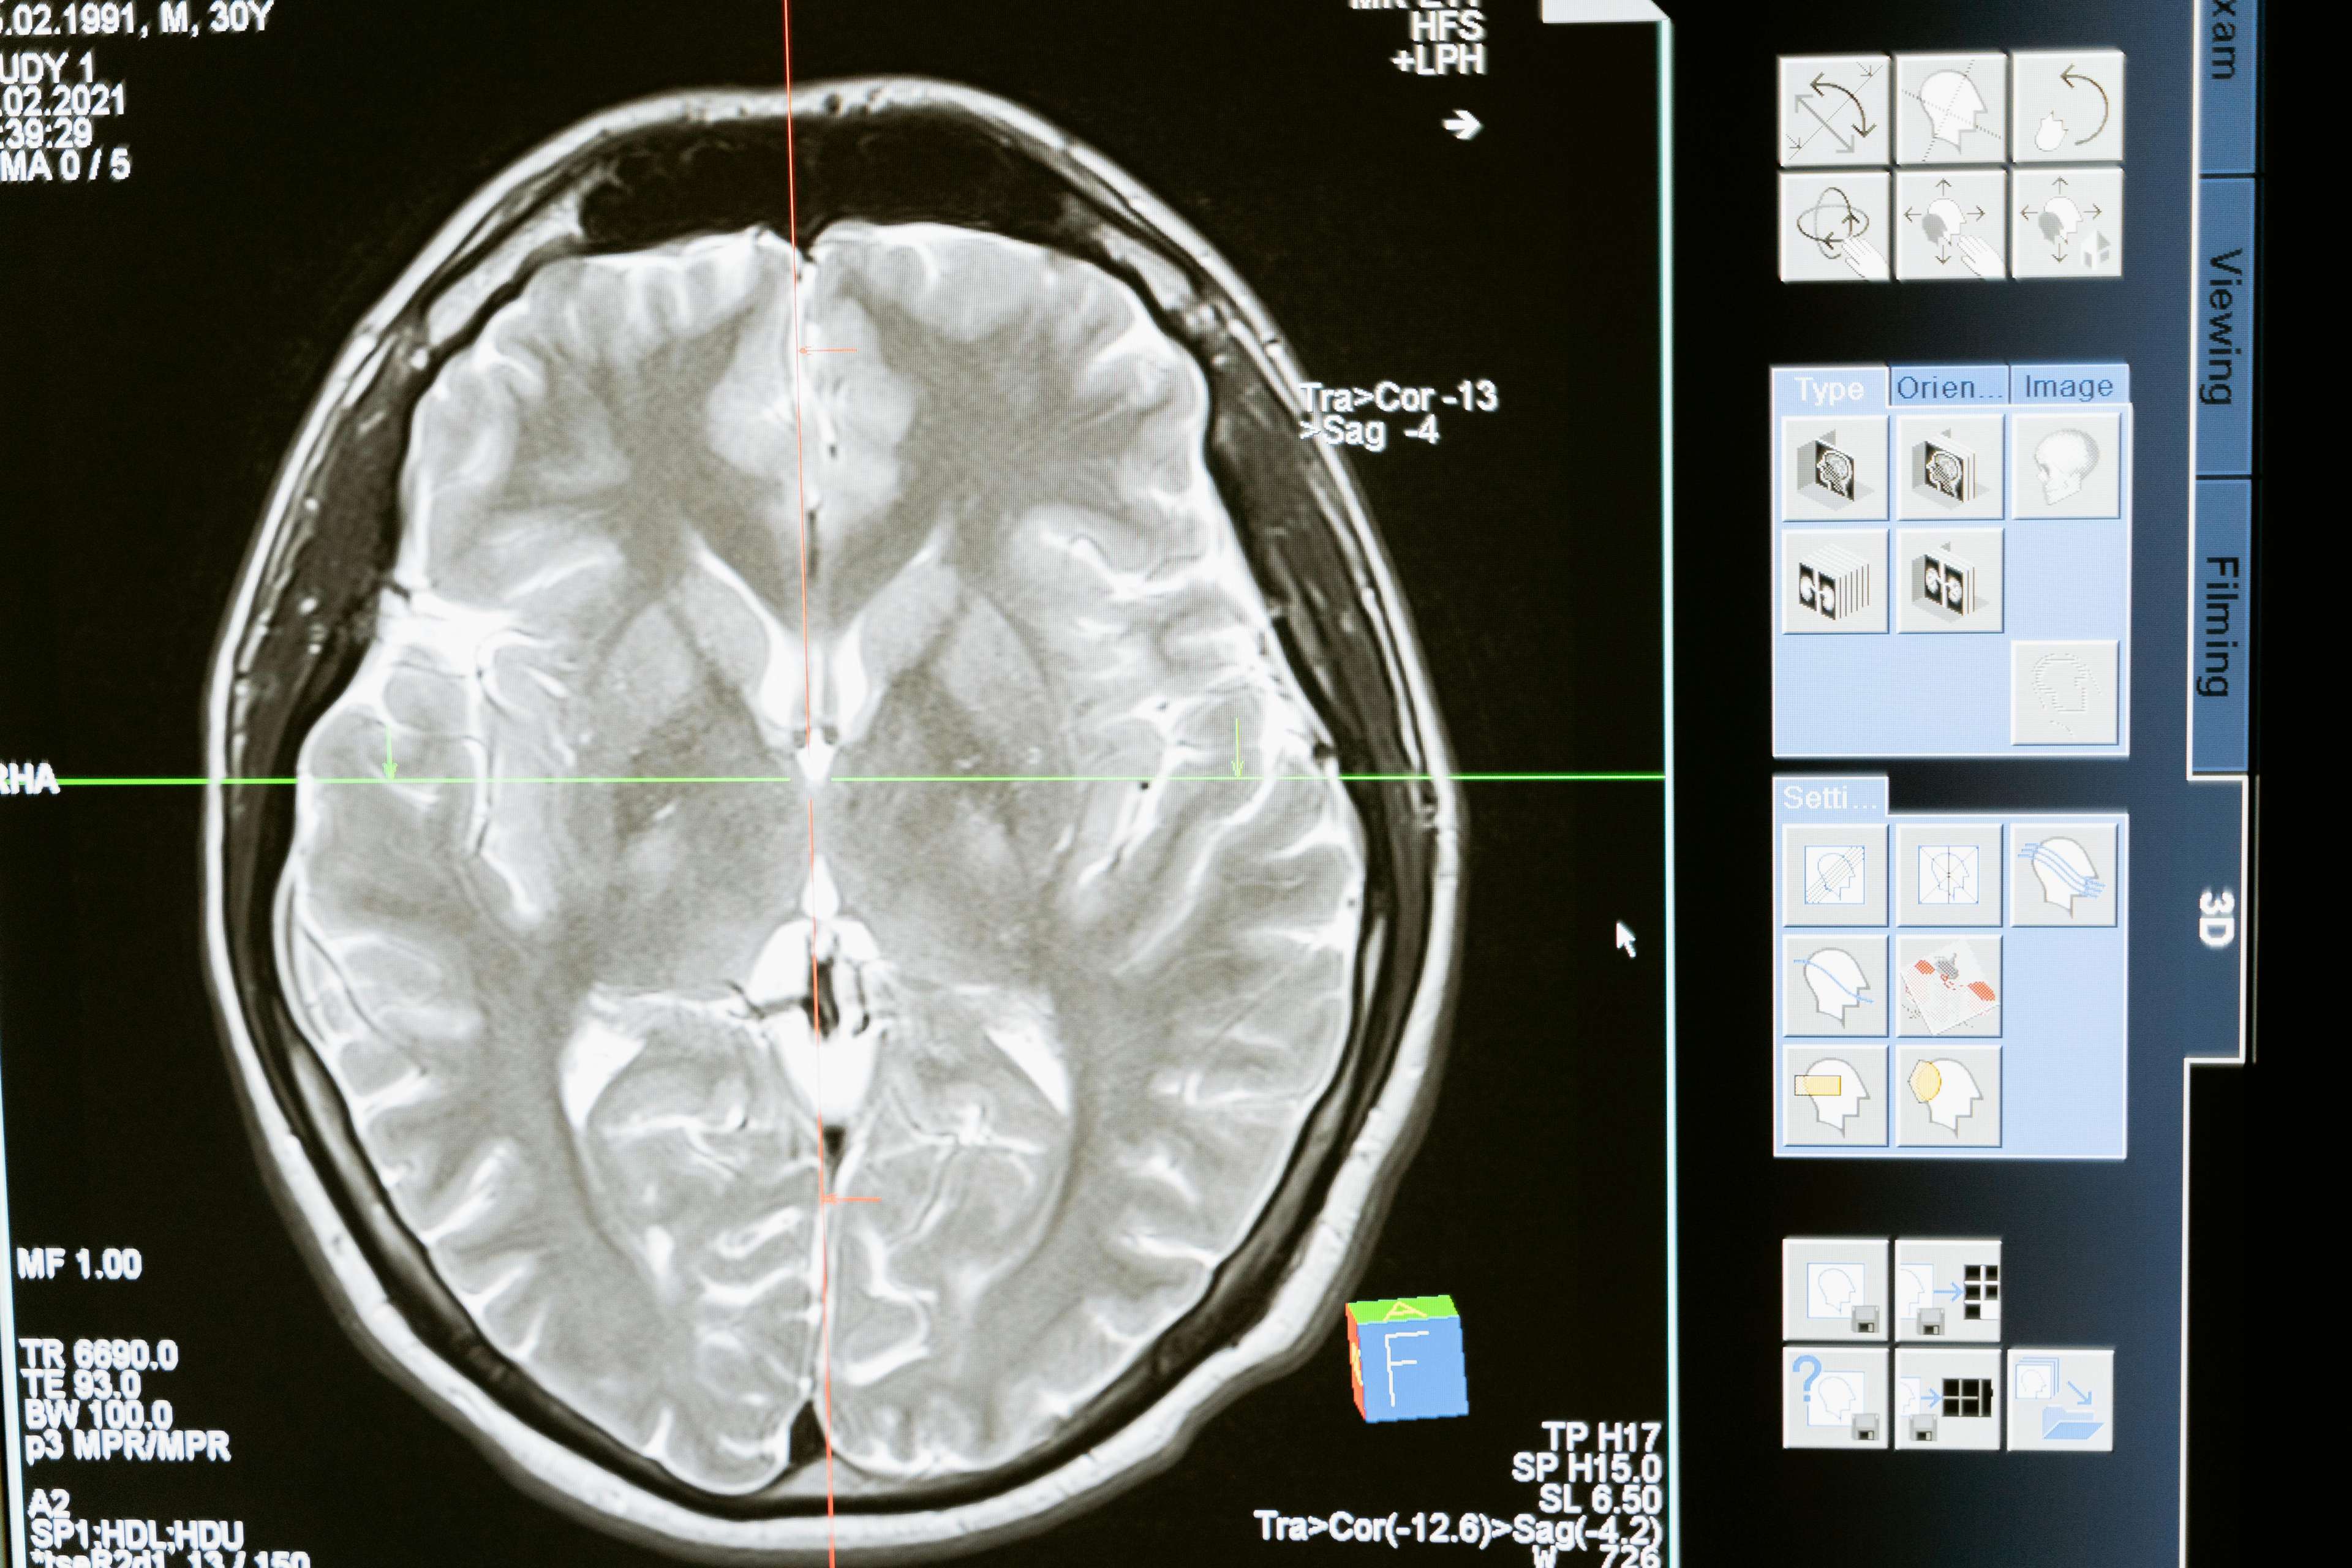

ጥልቅ የአንጎል ማነቃቂያ (DBS) የኤሌክትሪክ ግፊቶች ለተወሰኑ የአንጎል አካባቢዎች የኤሌክትሪክ ግፊቶች የመላክን መሳሪያ የሚያካትት የቀዶ ጥገና አሰራር ነው. ይህ ቴክኖሎጂ ለአስርተ ዓመታት ያህል ቆይቷል, ግን የቅርብ ጊዜ መጫዎቻዎች የበለጠ ውጤታማ, ተደራሽ እና ደህንነታቸው ያስደስተዋል. ቀደም ባሉት ጊዜያት ዲቢኤስ በዋናነት እንደ ፓርኪንሰን፣ ዲስቶኒያ እና አስፈላጊ መንቀጥቀጥ ያሉ የመንቀሳቀስ እክሎችን ለማከም ይጠቅማል. ነገር ግን፣ አፕሊኬሽኖቹ እንደ ኦብሰሲቭ ኮምፐልሲቭ ዲስኦርደር፣ ትልቅ የመንፈስ ጭንቀት እና አልፎ ተርፎም ሥር የሰደደ ሕመም ያሉ የአእምሮ ሕመሞችን ለማካተት ተዘርግተዋል. ሂደቱ በአእምሮ ውስጥ ኤሌክትሮክን መትከልን ያካትታል, ይህም የኤሌክትሪክ ግፊቶችን ከሚያመነጭ የልብ ምት መሰል መሳሪያ ጋር የተገናኘ ነው. እነዚህ ግፊቶች ያልተለመደ የአንጎል እንቅስቃሴን ይቆጣጠራሉ, ምልክቶችን ያቃልላሉ እና የህይወት ጥራትን ያሻሽላሉ.